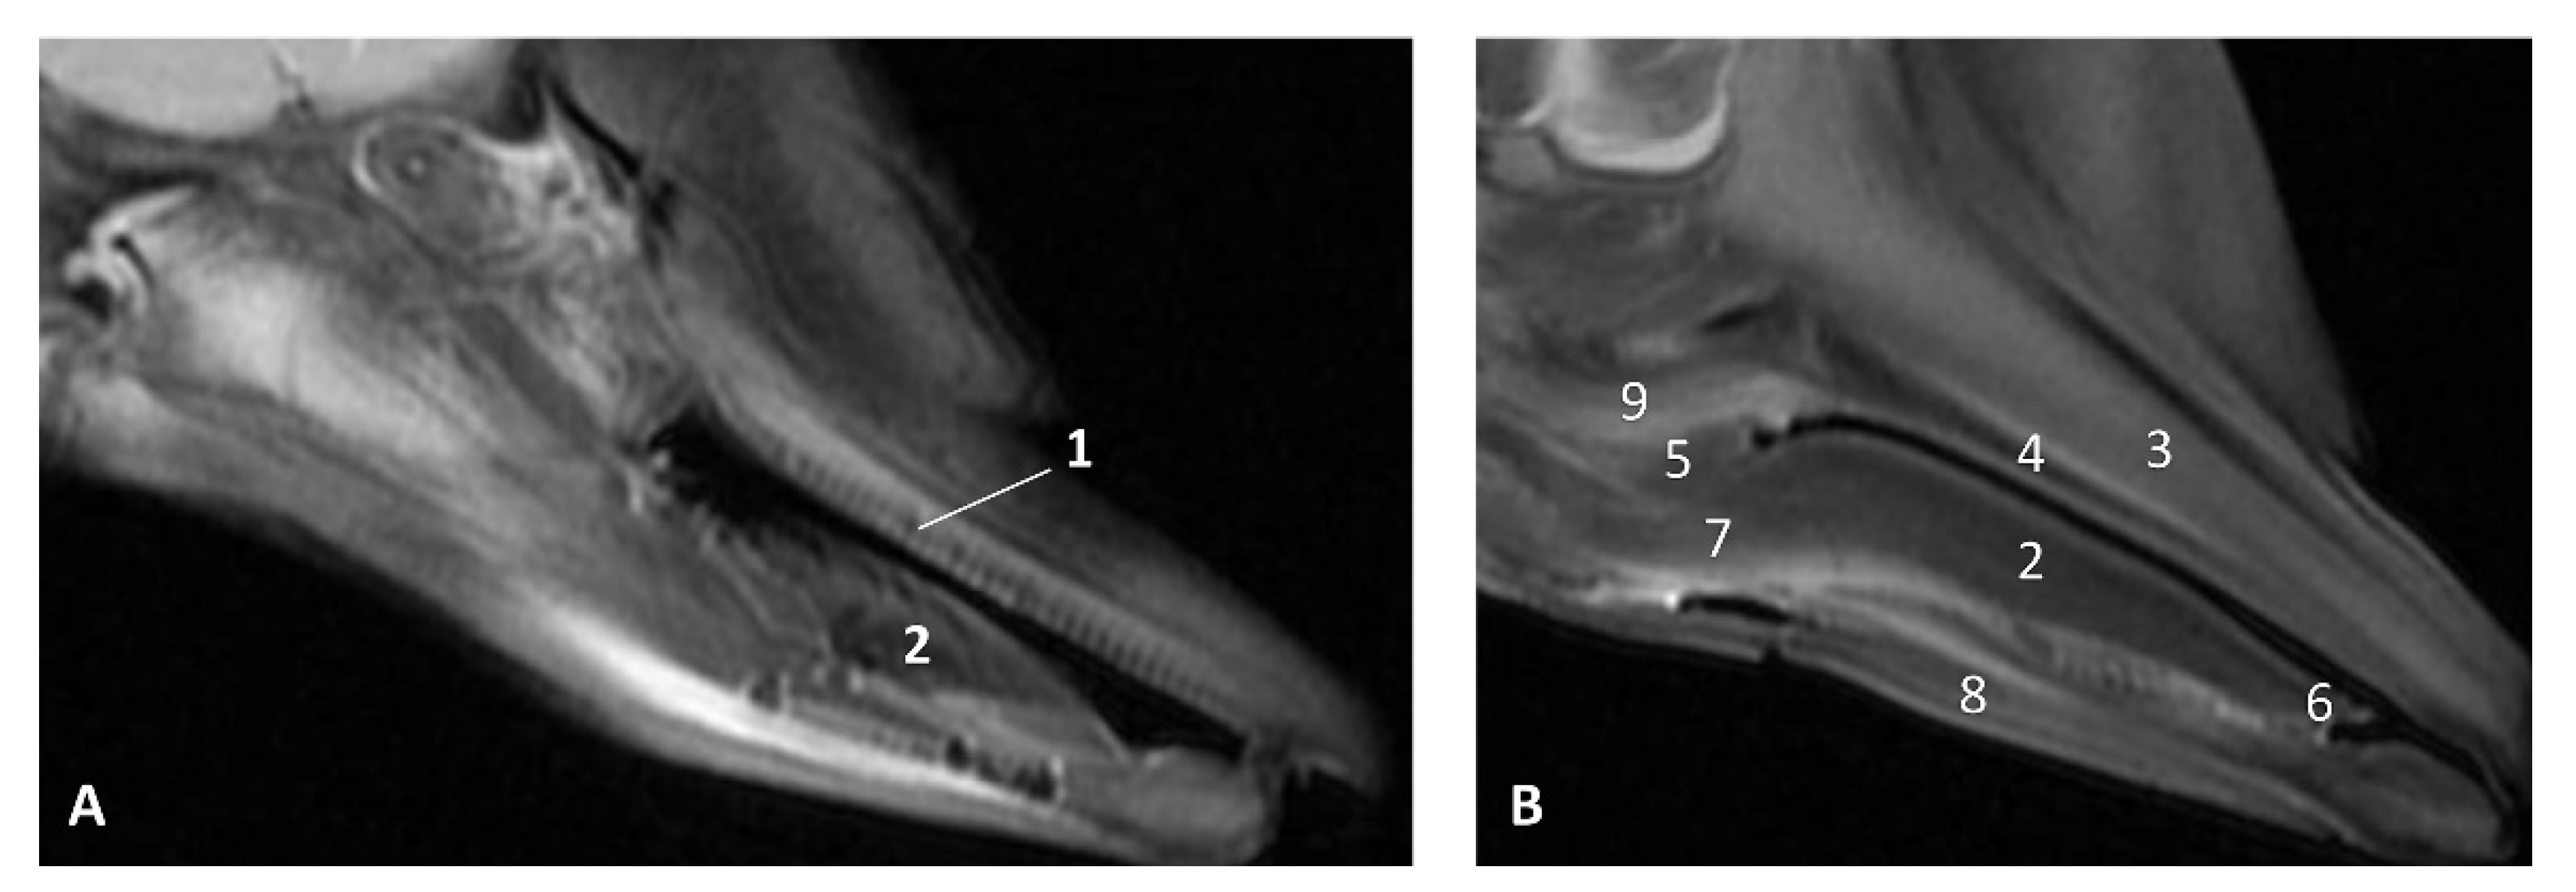

3.1.2. MRI Study

The T2 MRI image of the oral cavity in this Delphinus delphis (dde11) shows that the maxillary bone is medium hyperintense with respect to the hypointense hard palate. The superficial mucosa of tongue is slightly hyperintense with respect to the hypointense depressor, protractor and retractor muscles of the tongue. A hyperintense stratum under the tongue muscles is probably due to the high rate of irrigation of these muscles. We observed that non-erupted teeth can be seen under the gums (Figure 11).

Figure 11.

Images of the oral cavity. MR sagittal images is oriented so that the rostral is to the right. (A) T2 FrFSE sagittal plane. 6 months, dde8. Image of the oral cavity. (B) T2 FrFSE sagittal plane. Quadknee coil. 8 months, dde11. 1, Teeth (under gum); 2, Tongue: body; 3, Maxillary bone; 4, Hard palate; 5, Soft palate; 6, Tongue: apex; 7, Tongue: root; 8, Mandibles; 9, Pterygoid and palatine bones.